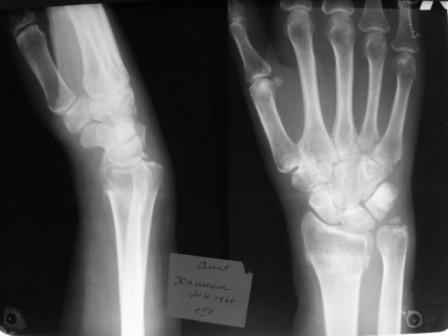

Уважаемые коллеги.Прошу обсудить случай лечения перелома дистального метаэпифиза лучевой кости. Ситуация скандальная и крайне неблагоприятная. Больная с патологической обстоятельностью мышления, склонностью к сутяжничеству, патологическими умозаключениями, не поддающимися коррекции (см. психиатрию, правда офиц. диагноза нет). В данном случае есть ряд ошибок с нашей стороны, прежде всего в отношении качества ведения документации (за что получил административное взыскание, по делом мне дураку). В остальном- придерживались в лечении подхода классический советской школы. Так как умную операцию…… сами знаете… 15.12- перелом луча в Москве. Там же репозиция, гипс. Дальнейшее лечение у нас в ЦРБ. 20.12.- вторичное смещение в гипсе21.12- под внутривенным наркозом- репозиция, гипсовая лонгета. Дальше начинается самое интересное. После репозиции больная заявила, что я (репозицию делал я) порвал ей все связки в суставе, посинел у нее 5 палец, якобы я за него тянул и т. д. На самом деле на 2 сутки после репозиции рука немного отекла и было незначительное сдавление гипсом, который был ослаблен. Дальнейшее лечение консервативное. Через 6 недель- гипс снят, назначено ЛФК. Пациентка крайне недовольна. Говорит, что на снимке у нее выступает кость, я ей сломал руку и.т.д. В общем началось. Пациентка прочитала в интернете наверное все, что есть по данной травме.По заключениями рентгенологов и консультанта из КДЦ областной больницы - стояние отломков допустимое. Объективно говоря- снижена высота лучевой кости, диастаз лучелоктевого сочленения, и не сросся шиловидный отросток. однако на РКТ при сравнении с другой стороной- разница незначительная. Дальше в одной из больниц нашей области и одной из больниц Москвы (вроде бы КГБ 53) врачи сказали, что репозиция сделана плохо. Нужна операция (восстановить длину лучевой кости), даже один из них предложил РЕДРЕССАЦИЮ (хи-хи) с наложением аппарата Илизарова. Что это для данной больной- радость неописанная. (см. описание психического статуса). Ничем другим, кроме зарабатывания дешевого авторитета объяснить данный факт не могу.Кстати, у больной еще нейропатия локтевого нерва.Для разрешения конфликта больная направлена на консультацию в ЦИТО на 03.03.11.

1. Репозиция от 21.12.10 была выполнена лучше, чем первичная.

Заключение: Консолидированный в неправильном положении перелом дистального метафиза левой лучевой кости. Ротационная контрактура левого предплечья. Рекомендовано- разработка, консультация через 2 месяца.

Объективно: пронация почти полная, супинация ограничена, ладонная флексия около 20, тыльная 10. Гипостезия в зоне инервации локтевого нерва. Незначительный отек. Хват кисти полный. Сила 4 балла.

В общем, типичная картина раннего восстановительного периода после снятия гипса. Визуально конечность не изменена.